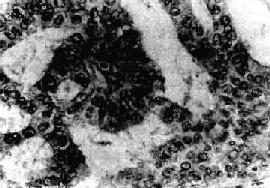

图13-7 子宫平滑肌

多个肌结节,位于肌壁内、粘膜下及浆膜下,境界分明,宫腔受挤压呈裂隙状